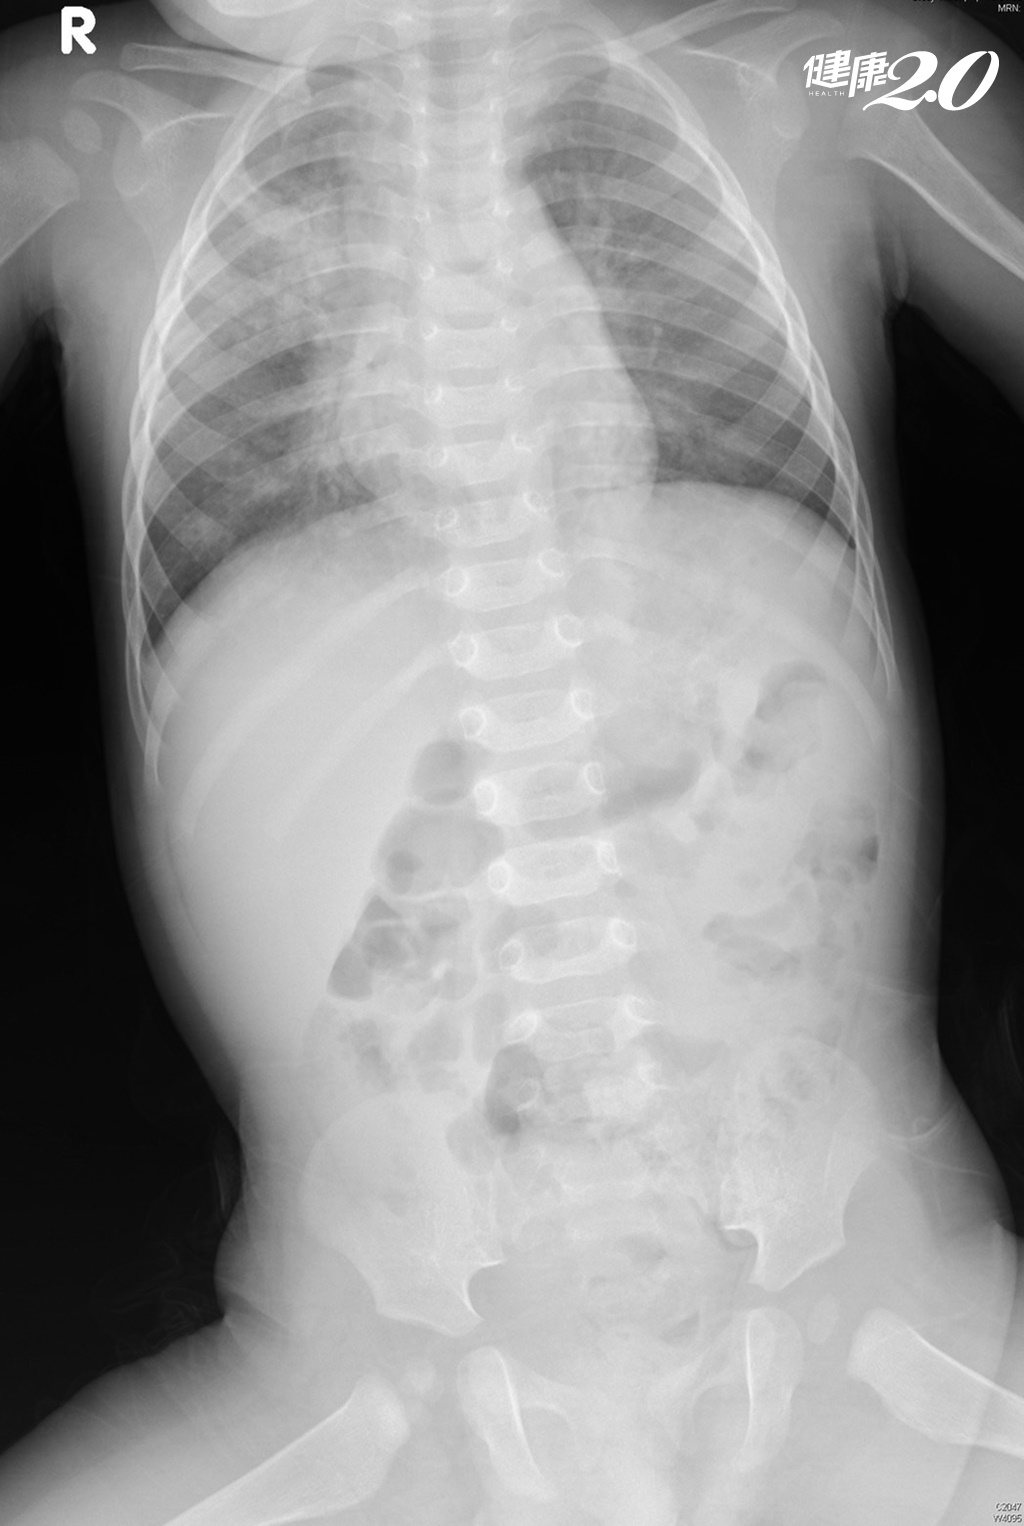

▲RSV感染的病人胸部X光片。(圖片提供/吳昌騰醫師)

吳昌騰醫師表示,大多數孩子在2 歲之前的某個時間點會感染RSV,每個人感染RSV的臨床表現不同,視病人年齡及健康狀況而定,症狀可能像普通感冒,在嬰兒及年紀小的兒童表現主要為咳嗽98%、發燒75%、流鼻涕、喘鳴65%~78%、費力呼吸73%~95%,高危險族群兒童若感染RSV可能會很危險,輕者咳嗽不止、脫水、細支氣管炎或肺炎、重者呼吸困難、呼吸衰竭、心肺衰竭等,更嚴重者甚至需要插管或使用葉克膜。

黃立民醫師也說明,RSV是一種特別容易造成下呼吸道感染的病毒,最主要的症狀是發燒、咳嗽,而且呼吸很喘,比一般感冒更為嚴重,容易引發細支氣管炎。RSV主要侵犯5歲以下小孩,尤其2歲以下嬰幼兒,由於支氣管太細,會在呼吸時出現「咻咻咻」的哮喘聲,以及類似氣喘的狀況,呼吸困難,很多必須住院用氧氣、並給予點滴補充水分。若放任病情,可能需要1~2周才會自行痊癒,對有慢性病或心臟病的小朋友,甚至可能造成窒息死亡。